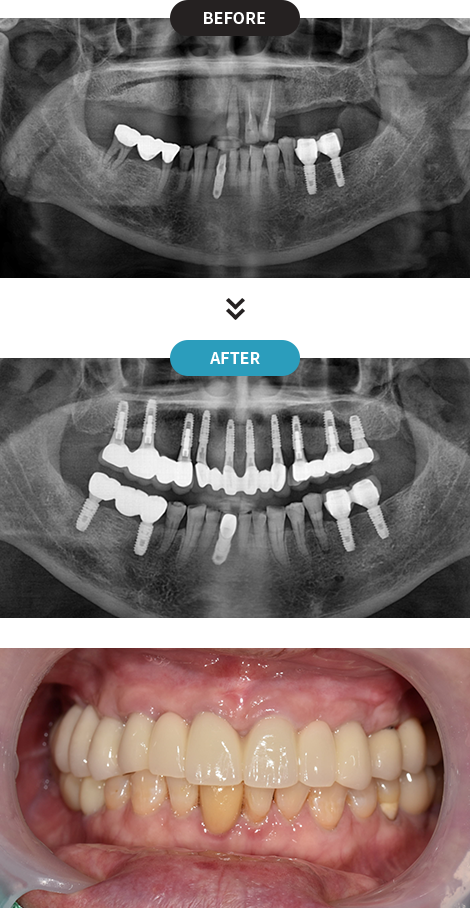

3D디지털 스캔을 활용하여 가장 안전하게 임플란트를

식립할 수 있는 위치를 0.1mm 오차까지 정확하게 계산합니다.

제작된 보철물을 모의 수술을 통해 정해진 임플란트 식립 위치에 빠르고 정확하게 식립합니다.